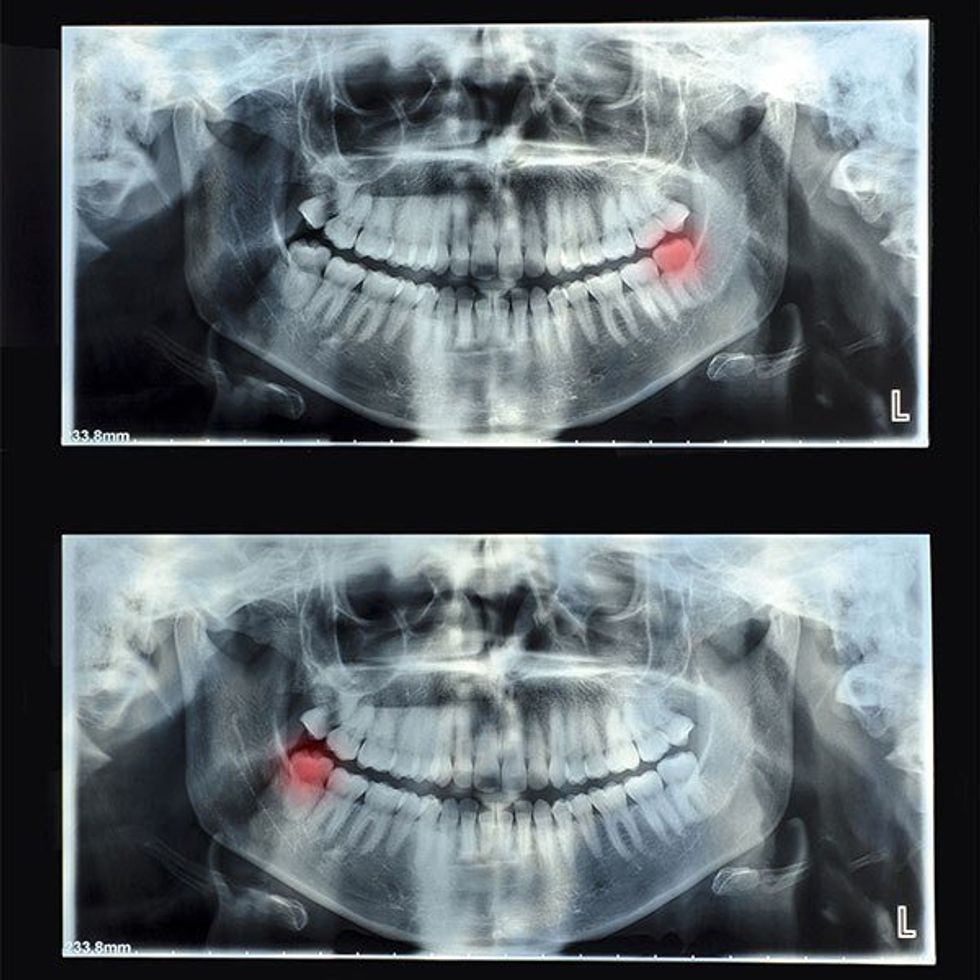

What little wisdom I had has left me for some supposed greater good, or so my dentist claims. I have a running theory that dentists are storing all of our wisdom to take over the world.

Except I don't. Because, I don't know if you've ever had your wisdom teeth removed, but that hurts like a son of a bitch.